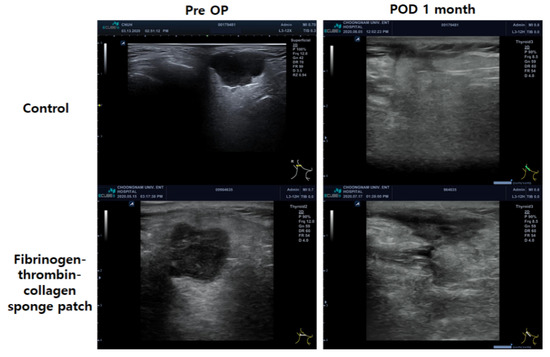

3.4. Postoperative Evaluation of Surgical Bed Using Ultrasonography